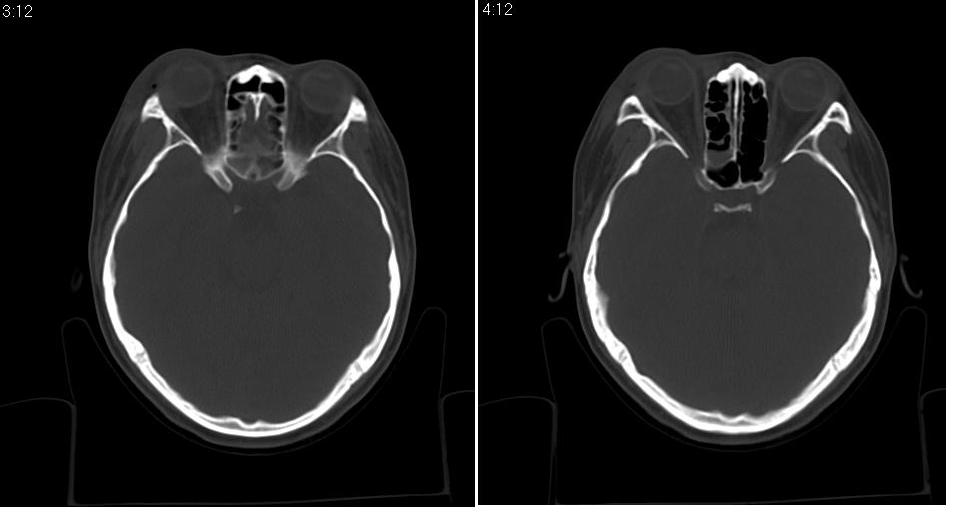

标题: CT9542:鼻窦CT平扫 [打印本页]

标题: CT9542:鼻窦CT平扫

女 18岁,外伤.

右侧上颌窦前壁骨折,窦腔积液.

右侧上颌窦前后壁及右颧骨弓骨折,窦腔积液。

右侧上颌窦前后壁骨质均不连续,窦腔内见一致性高密度影,右睑部软组织肿胀

1,右上颌窦前后壁骨折,伴窦腔积血可能性大

2,右睑部软组织肿胀

右侧上颌窦前壁、外侧壁、内侧壁骨折,伴窦腔积液;右侧颧弓骨折。

1 、 右侧上颌窦前壁、外侧壁、内侧壁骨折并窦腔积液(血);右侧上颌窦前壁骨折累及同侧鼻泪管;

2、右侧颧骨骨折。

右侧上颌窦前后壁及颧弓骨质均不连续,窦腔内见一致性高密度影,右面部及眼睑部软组织肿胀

1,右上颌窦前后壁骨折伴窦腔积血,右侧颧弓骨折.

2,右面部及眼睑部软组织肿胀